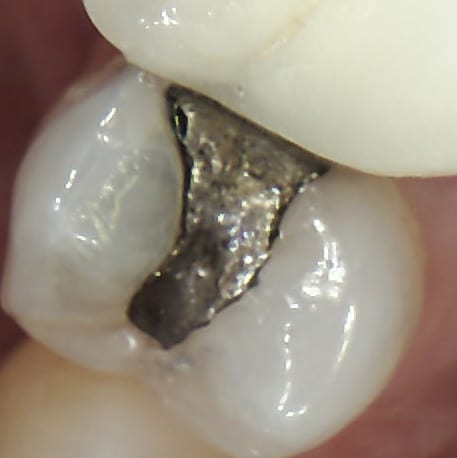

Margin Gap Amalgam Filling

Margin Gap

A margin gap is a leakage between the filling and the tooth. This allows bacteria to enter and cause decay, often without producing any immediate pain.